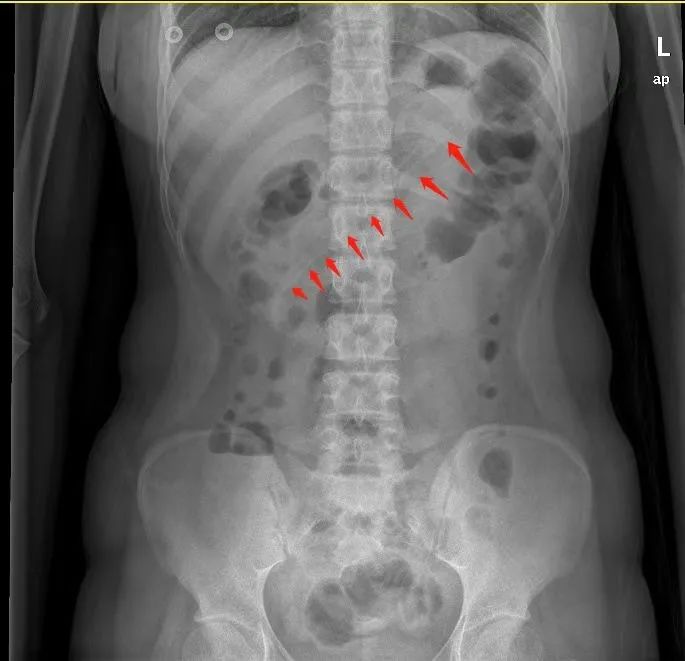

腹部X线检查显示,小李胃中的勺子长达17厘米,因此胃镜下取异物有较大的难度。但如果不取出,患者可能会出现消化道梗阻、出血和穿孔等并发症。因此,胃镜下取出异物势在必行。

术前,黄晓春主任进行了充分的术前告知后,患者及家属签字同意。与此同时,胃镜室与麻醉科也提前拟定了多个可能的方案,并知会耳鼻喉科和胃肠外科做好准备。术中,实施无痛麻醉后,在医生操作下,胃镜快速就位。通过胃镜,一进入胃腔就能看到一根长长的塑料勺子横跨在胃体至十二指肠球部。

黄晓春主任一开始选择用异物钳钳夹异物,但因为太大了无法夹住,给手术进行带来了一定难度。随后,她改用圈套器,尝试套住异物。但因异物两端顶住胃腔和十二指肠球腔,要想套住异物并不容易。经过不断地调整圈套的方向,终于套住了勺子合适的位置,顺着胃食管纵轴缓缓取出。